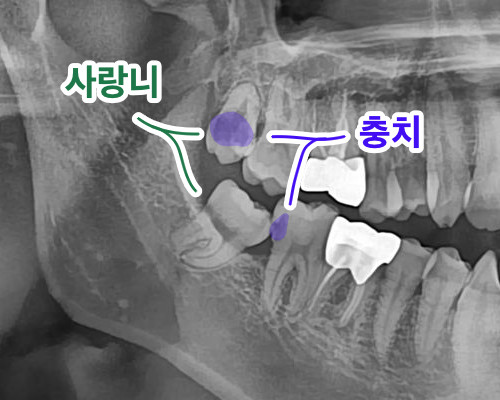

기울어져서 난 아래 사랑니

제일 뒤쪽에 있는 사랑니는 양치질이 잘 안되기 때문에 충치가 생기기도 하고,

아니면 공간이 부족해서 기울어져서 난 덕분에 사랑니 앞 치아에 충치가 생기기도 합니다